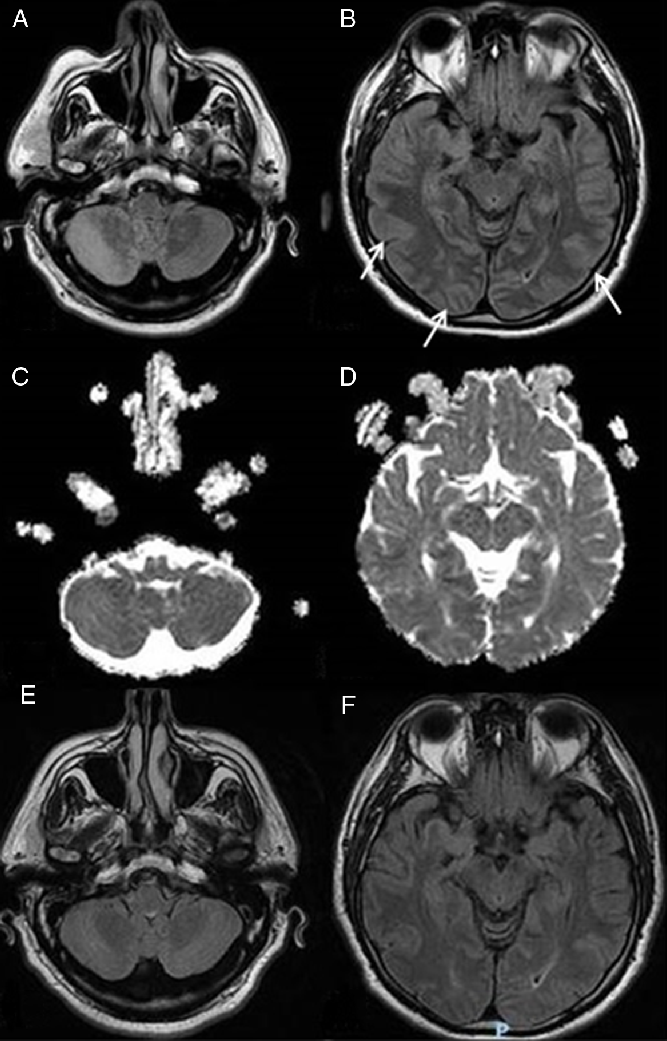

A chest X-ray was negative for consolidations or interstitial involvement; the head computed tomography (CT) angiography was negative for major vessel occlusion or ischemia, while magnetic resonance imaging (MRI) showed diffusion-weighted imaging (DWI) and fluid attenuated inversion recovery (FLAIR) hyperintense lesions in the right cerebellar hemisphere and in the vermis and further alterations in the occipital parietal cortex bilaterally (Figure 1A and B) with normointense ADC maps (Figure 1C and D) suggestive of posterior vasogenic edema.

Figure 1: MRI findings at the acute onset and at the follow-up. (A and B) FLAIR MRI scans showing lesions of the right cerebellar hemisphere and of the cerebellar vermis and in the parieto-occipital lobes at the acute onset (arrows pointing at the parieto-occipital lesions). (C and D) Normointense ADC maps at the acute onset. (E and F) FLAIR MRI sequences showing a complete resolution of the lesions at the follow-up MRI.

At the admission to the department of infectious diseases, 24 h later, the patient was stuporous but easily awakened in response to verbal stimuli, well oriented to place but not in time. Bilateral visual impairment was still present, though an initial recovery of left lateral visual field was reported. Fever ceased on the second day of hospitalization. The antibiotic therapy was continued because of the suspicion of a procedure-related sepsis and maintained for a 14-days cycle; antivirals were continued because of the possibility of an overlapping encephalitis. A full recovery of the visual acuity (20/20 in both eyes) and an improvement of the neurological examination occurred on the 9th day. A transthoracic echocardiogram showed no vegetations, blood cultures performed in the ER were sterile, polymerase chain reaction (PCR) for genome of neurotropic viruses from a CSF sample was negative and a clinical ophthalmic evaluation showed no abnormalities. A second brain MRI evaluation performed 14 days later showed a complete resolution of the initial alterations (Figure 1E and F). A neurologic evaluation showed normal visual-spatial perceptive functions. The patient was discharged with the indication of a further outpatient neurologic evaluation that confirmed the complete clinical remission.

This article describes a case of headache, encephalopathy, nausea, vomiting, cortical blindness, memory impairment, and restlessness a few minutes after an intramuscular injection of OOT with complete recovery in 9 days. The brain MRI findings at the clinical onset were consistent with vasogenic edema in the parieto-occipital area that completely receded at the following MRI examination 15 days later. The clinical and radiological findings are suggestive for a posterior reversible encephalopathy syndrome (PRES).Reference Hinchey, Chaves and Appignani1